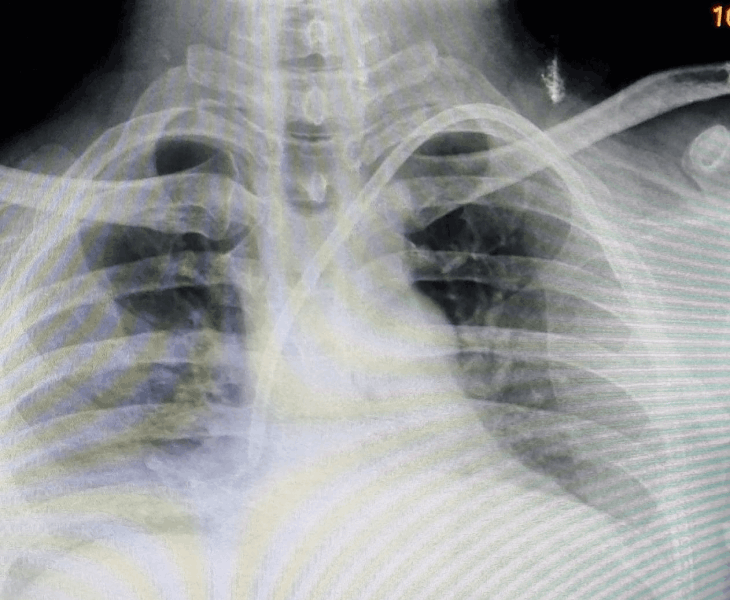

After placement, a chest X‑ray may be used to confirm position and rule out complications.

Perm cath insertion